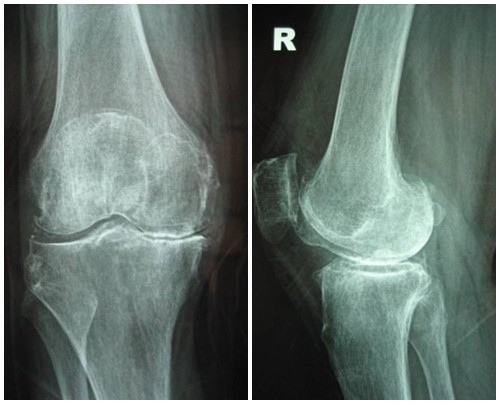

Hình ảnh của khớp gối trên phim X-quang: Khe khớp hẹp rõ, nhiều gai xương kích thước vừa, đặc xương dưới sụn, đầu xương có thể bị biến dạng.

Thoái hóa khớp gối tiến triển đến giai đoạn 3 thì bệnh nhân sẽ càng cảm nhận rõ những cơn đau tại khớp gối. Các lớp sụn khớp bao bọc các đầu xương bị bào mòn nhiều và khoảng không gian giữa các đầu xương bị thu hẹp thấy rõ. Khả năng đi bộ của người bệnh giảm, đi, đứng, ngồi xổm, lên xuống cầu thang cũng thấy đau. Tình trạng cứng khớp vào buổi sáng cũng xảy ra thường xuyên hơn kèm theo các đợt viêm khớp gối (sưng, đau, tràn dịch) hoặc có biểu hiện vẹo khớp gối.

Hình ảnh của khớp gối trên phim X-quang: Khe khớp hẹp nhiều, gai xương có kích thước lớn, đặc xương dưới sụn, đầu xương biến dạng rõ.

Thoái hóa khớp gối đã bước vào giai đoạn nặng, sụn khớp bị bào mòn và bong tróc gần như hoàn toàn để lộ đầu xương rõ rệt. Khoảng không gian chung giữa hai đầu xương thu hẹp đáng kể, gai xương ngày càng lớn, chất nhờn bôi trơn khớp giảm nên gây ra hiện tượng ma sát giữa hai đầu xương, gây đau nhức xương khớp nghiêm trọng. Người bệnh xuất hiện một loạt các triệu chứng đau nhức liên tục, cứng khớp, khó vận động khớp, khó đi lại… ảnh hưởng đến sinh hoạt. Theo thời gian, thoái hóa khớp gối có thể gây biến dạng khớp hoàn toàn, gây lệch trục khớp…